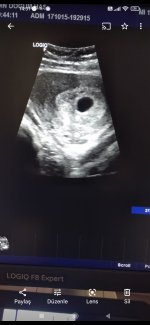

Merhabalar bayadir giriş yapmıyordum . herkese selamlar. Ben 1 hafta önce hamile olduğumu öğrendim. Ve şuan 6+2 günlük olduk. Ama iki gün önce 6+0 da kese gozukdu .ben kesenin içinde iki tane yuvarlak görüyorum sizce de öyle değil mi yorumlarsanız çok sevinirim

Cnm Allah sağlıkla kucağına alırsın banada ikiz gibi geldi

Bir tane kese görünüyor canım

Kızlar bugün hastaneye gittim karindqn 5+3 günlük dedi. Geçen hafta gittim .Altan muayne 6+0 dedi anlqmqdim .birde kese boyutu 15 mm olmuştu .geçen hafta 10.5 kesede büyümüş ama şuan 7 haftalık olmam lazım. Doktor bir öyle diyor bir böyle